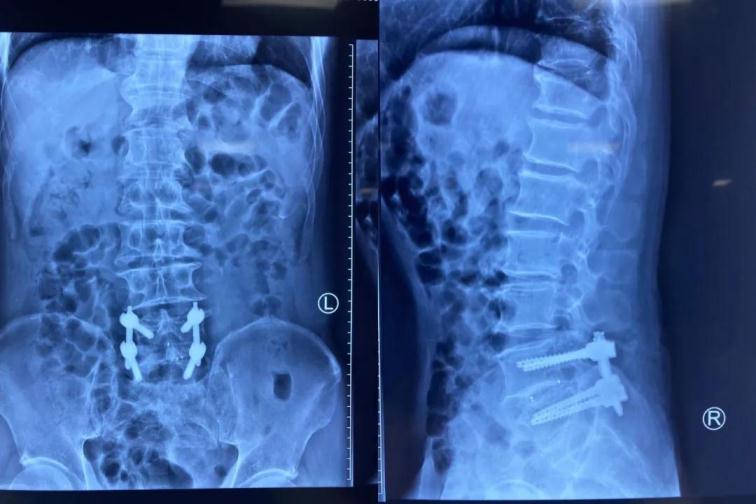

經(jīng)皮椎弓根螺釘內(nèi)固定

術(shù)后復(fù)查

與傳統(tǒng)的腰椎后路開放減壓手術(shù)及通道下的MIS-TLIF手術(shù)相比,經(jīng)脊柱內(nèi)鏡后路腰椎ENDO-TLIF手術(shù),創(chuàng)傷更小,神經(jīng)根及硬膜囊顯露清晰,且最大限度的保護(hù)了脊柱骨骼、韌帶及肌肉的完整性,對脊柱運動單元穩(wěn)定性影響較小,術(shù)后患者感受更佳,康復(fù)更快。目前,該患者術(shù)后癥狀消失,已經(jīng)能夠行走自如,對治療效果非常滿意。

我院骨科已多次成功開展脊柱內(nèi)鏡下經(jīng)椎間孔入路/后路腰椎體融合術(shù)及經(jīng)皮椎弓根釘內(nèi)固定術(shù) (Endo-T/PLIF),此項技術(shù)創(chuàng)傷小、恢復(fù)快,鏡下融合效果確切。本地區(qū)還沒有開展的先例。未來,佳木斯大學(xué)宏大醫(yī)院骨科團隊將繼續(xù)努力,讓脊柱微創(chuàng)技術(shù)造福更多三江地區(qū)廣大患者。